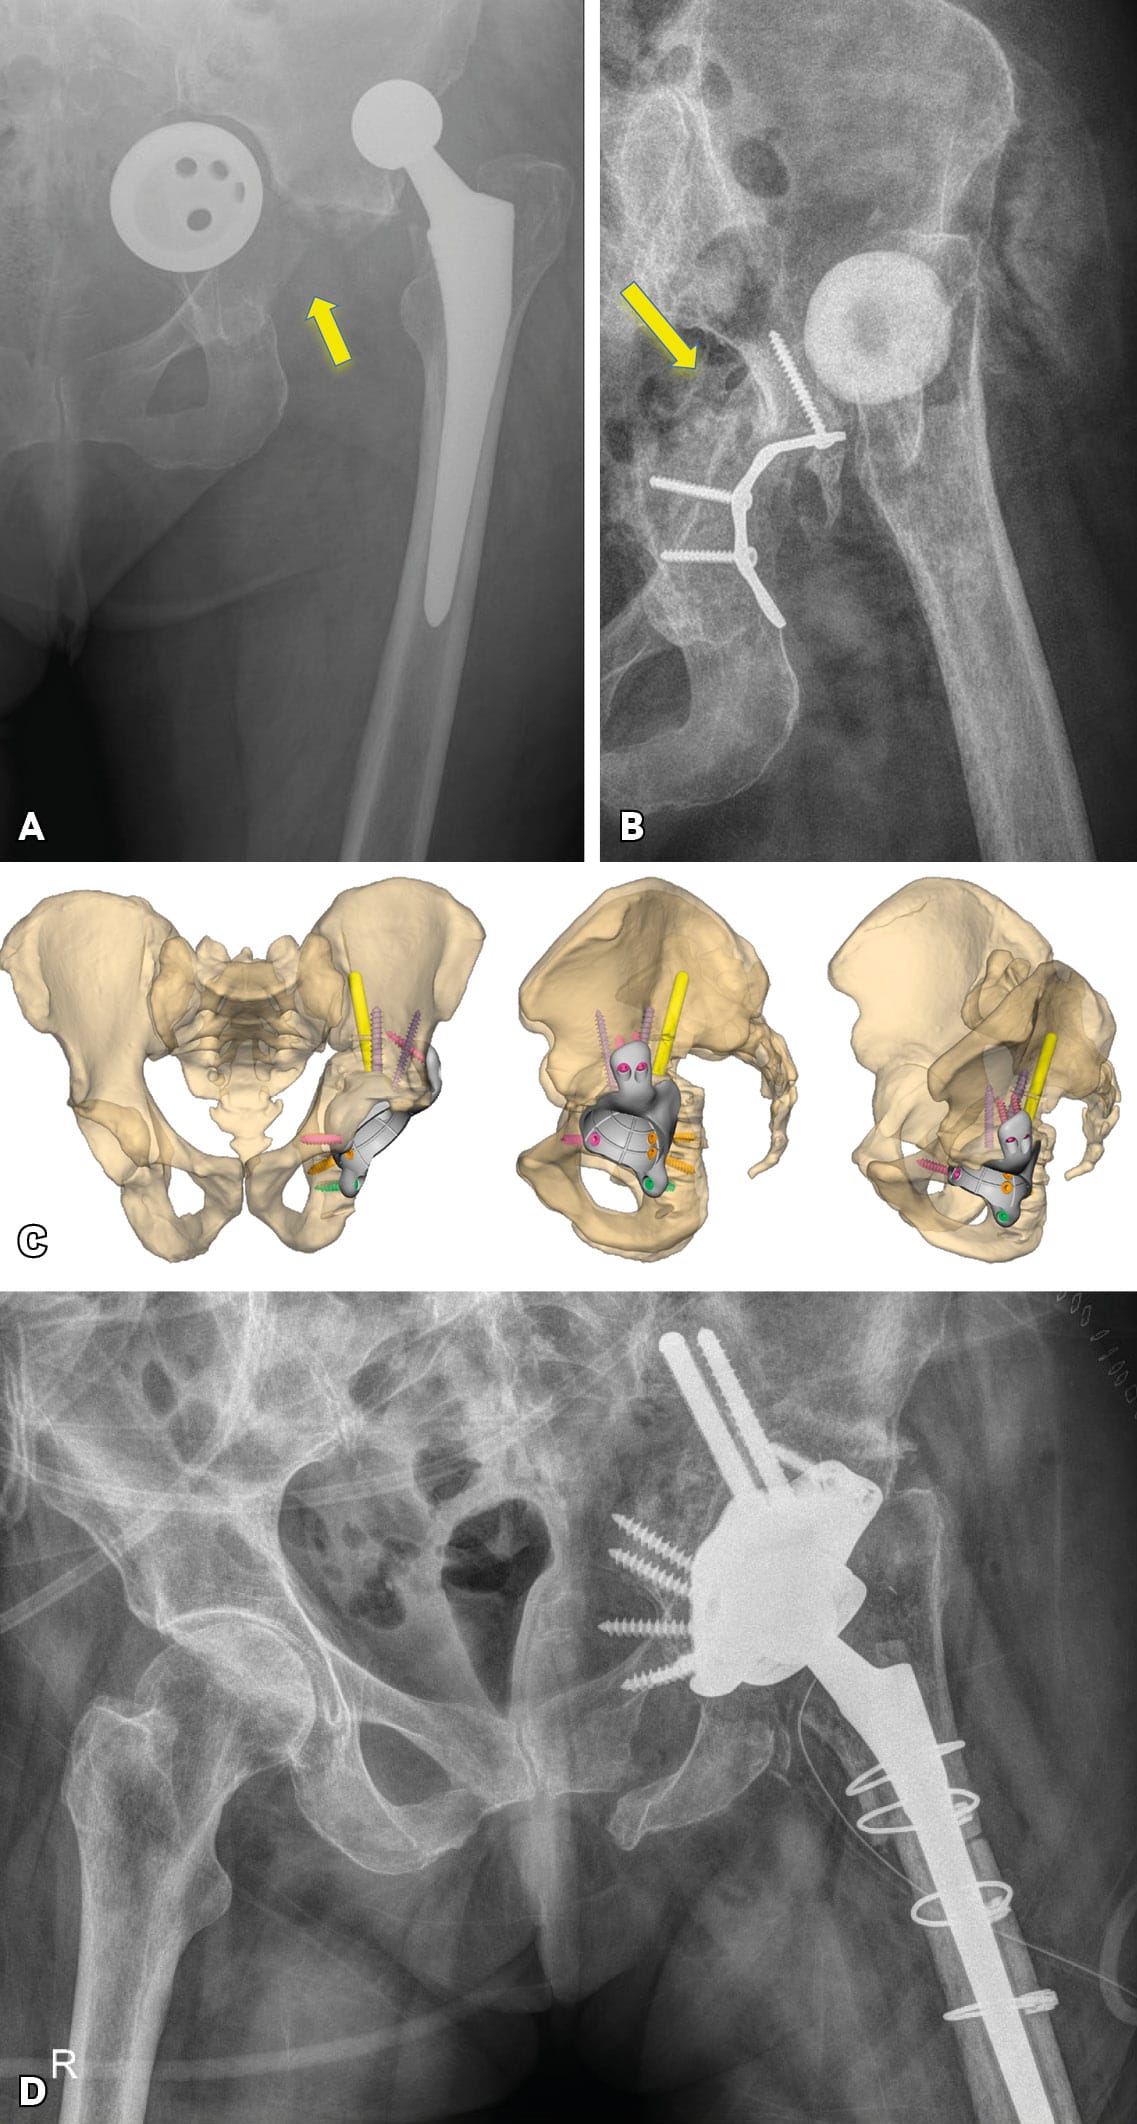

A classification system should accurately describe the problem, assist pre-operative evaluation and surgical pre-operative planning, and should predict outcomes. The recent Sen et al classification of late post-traumatic acetabular defects clearly reveals the patterns of post-traumatic nonunions and malunions.[1] Sen RK, Mukhopadhyay R, Pattanshetti V, Saini G, Tripathy SK, Sethy SS, Sharma SK. A New Classification System for Acetabular Bone Defect Evaluation in Posttraumatic Acetabular Nonunion and Malunion. Indian J Orthop. 2022 Jun 27;56(9):1601-1612 In the commonly used Paprosky classification, PD is often associated with IIIB and infrequently with IIC and IIIA bone defects.[4] Paprosky WG, Perona PG, Lawrence JM. Acetabular defect classification and surgical reconstruction in revision arthroplasty. A 6 year follow up evaluation. J Arthroplasty. 1994;9(1)33-34. However, the Paprosky classification fails to describe post-traumatic defects, and occasionally, orthopaedic surgeons encounter other acetabular bone defects which are not described by existing classification systems (Figure 1).

Severe post-operative defects. Principles of management and outcomes of specific patterns are not clearly reported in the literature. Based on the Sen clacification,[1] Sen RK, Mukhopadhyay R, Pattanshetti V, Saini G, Tripathy SK, Sethy SS, Sharma SK. A New Classification System for Acetabular Bone Defect Evaluation in Posttraumatic Acetabular Nonunion and Malunion. Indian J Orthop. 2022 Jun 27;56(9):1601-1612 types 1, 2, 3-A and 5 can be treated with surgical techniques used in revision THA surgery. For severe defects (such as 3-B, 4-A and 4-B), the restoration of hip center of rotation, cup offset, inclination and anterversion and hip stability can be achived only with custom-made implants (Figures 3 and 4).